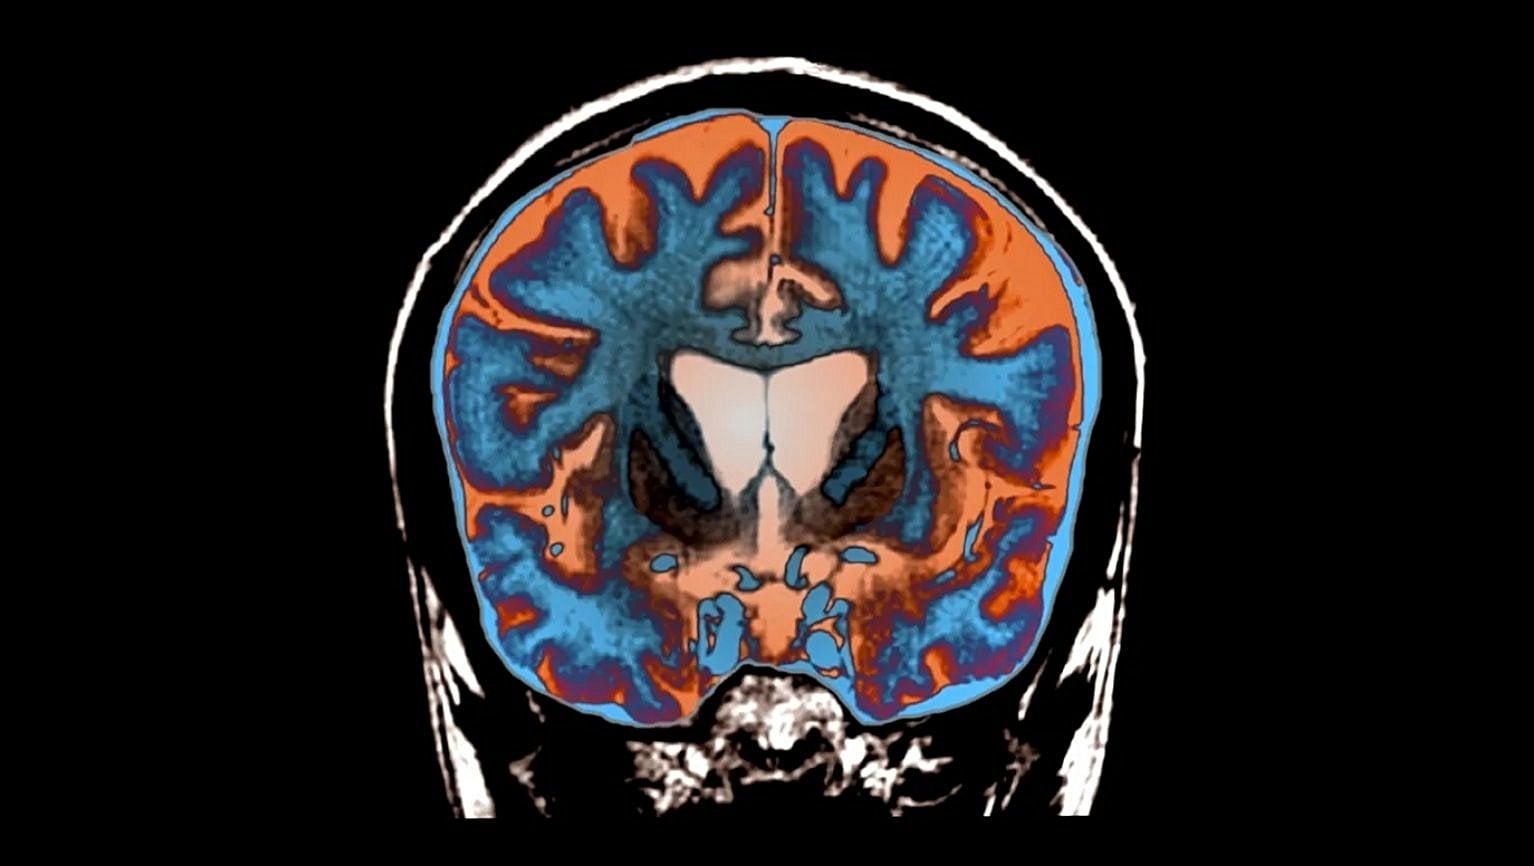

Esasen genişlemiş huntingtin, toksikleşmiş bir tür proteindir. Beyinde birikir ve özellikle istemli hareketler için kritik olan bölgelerdeki hücreleri öldürür. Hastalarda istemsiz hareketler artar; katılık, konuşma ve yutma güçlüğü ile bilişsel gerileme gelişir.